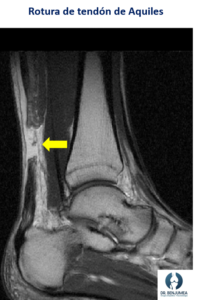

La Resonancia magnética es útil para evaluar la extensión de la rotura y el estado general del tendón y los músculos circundantes. Se utiliza cuando el diagnóstico no es claro con otras herramientas de imagen.